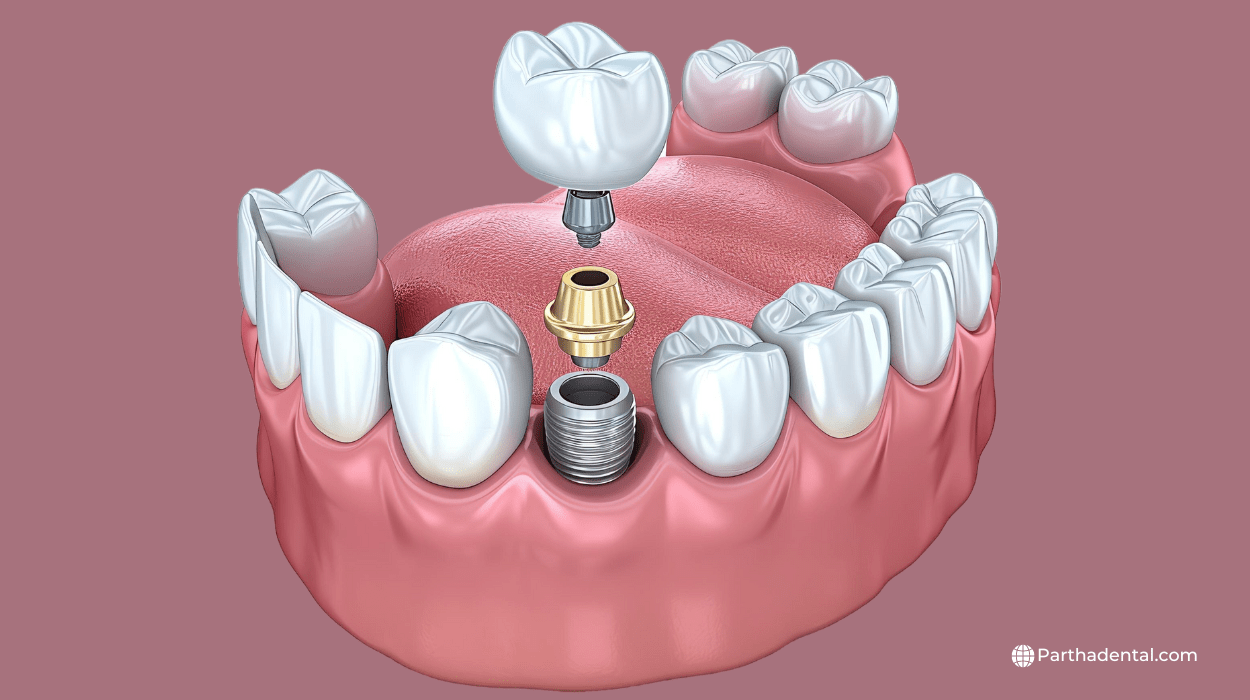

Dental implants are small, metal posts that are placed in your jawbone to replace missing teeth. They act like the roots of your natural teeth and provide a strong foundation for a new tooth, called a crown, which is attached on top. Dental implants look and feel like real teeth, making it easier to eat, talk, and smile. They are a popular choice for people who have lost teeth and want a long-lasting solution that helps keep their mouth healthy and their smile looking natural.

Endosteal Implants: These are the most common type, placed directly into the

jawbone. They are typically shaped like small screws.

Implant Placement: During the procedure, the dentist places the metal post into

your jawbone. This is done under local anesthesia to keep you comfortable.

Abutment Placement: Once the implant is secure, the dentist attaches a small

connector piece called an abutment to the implant.